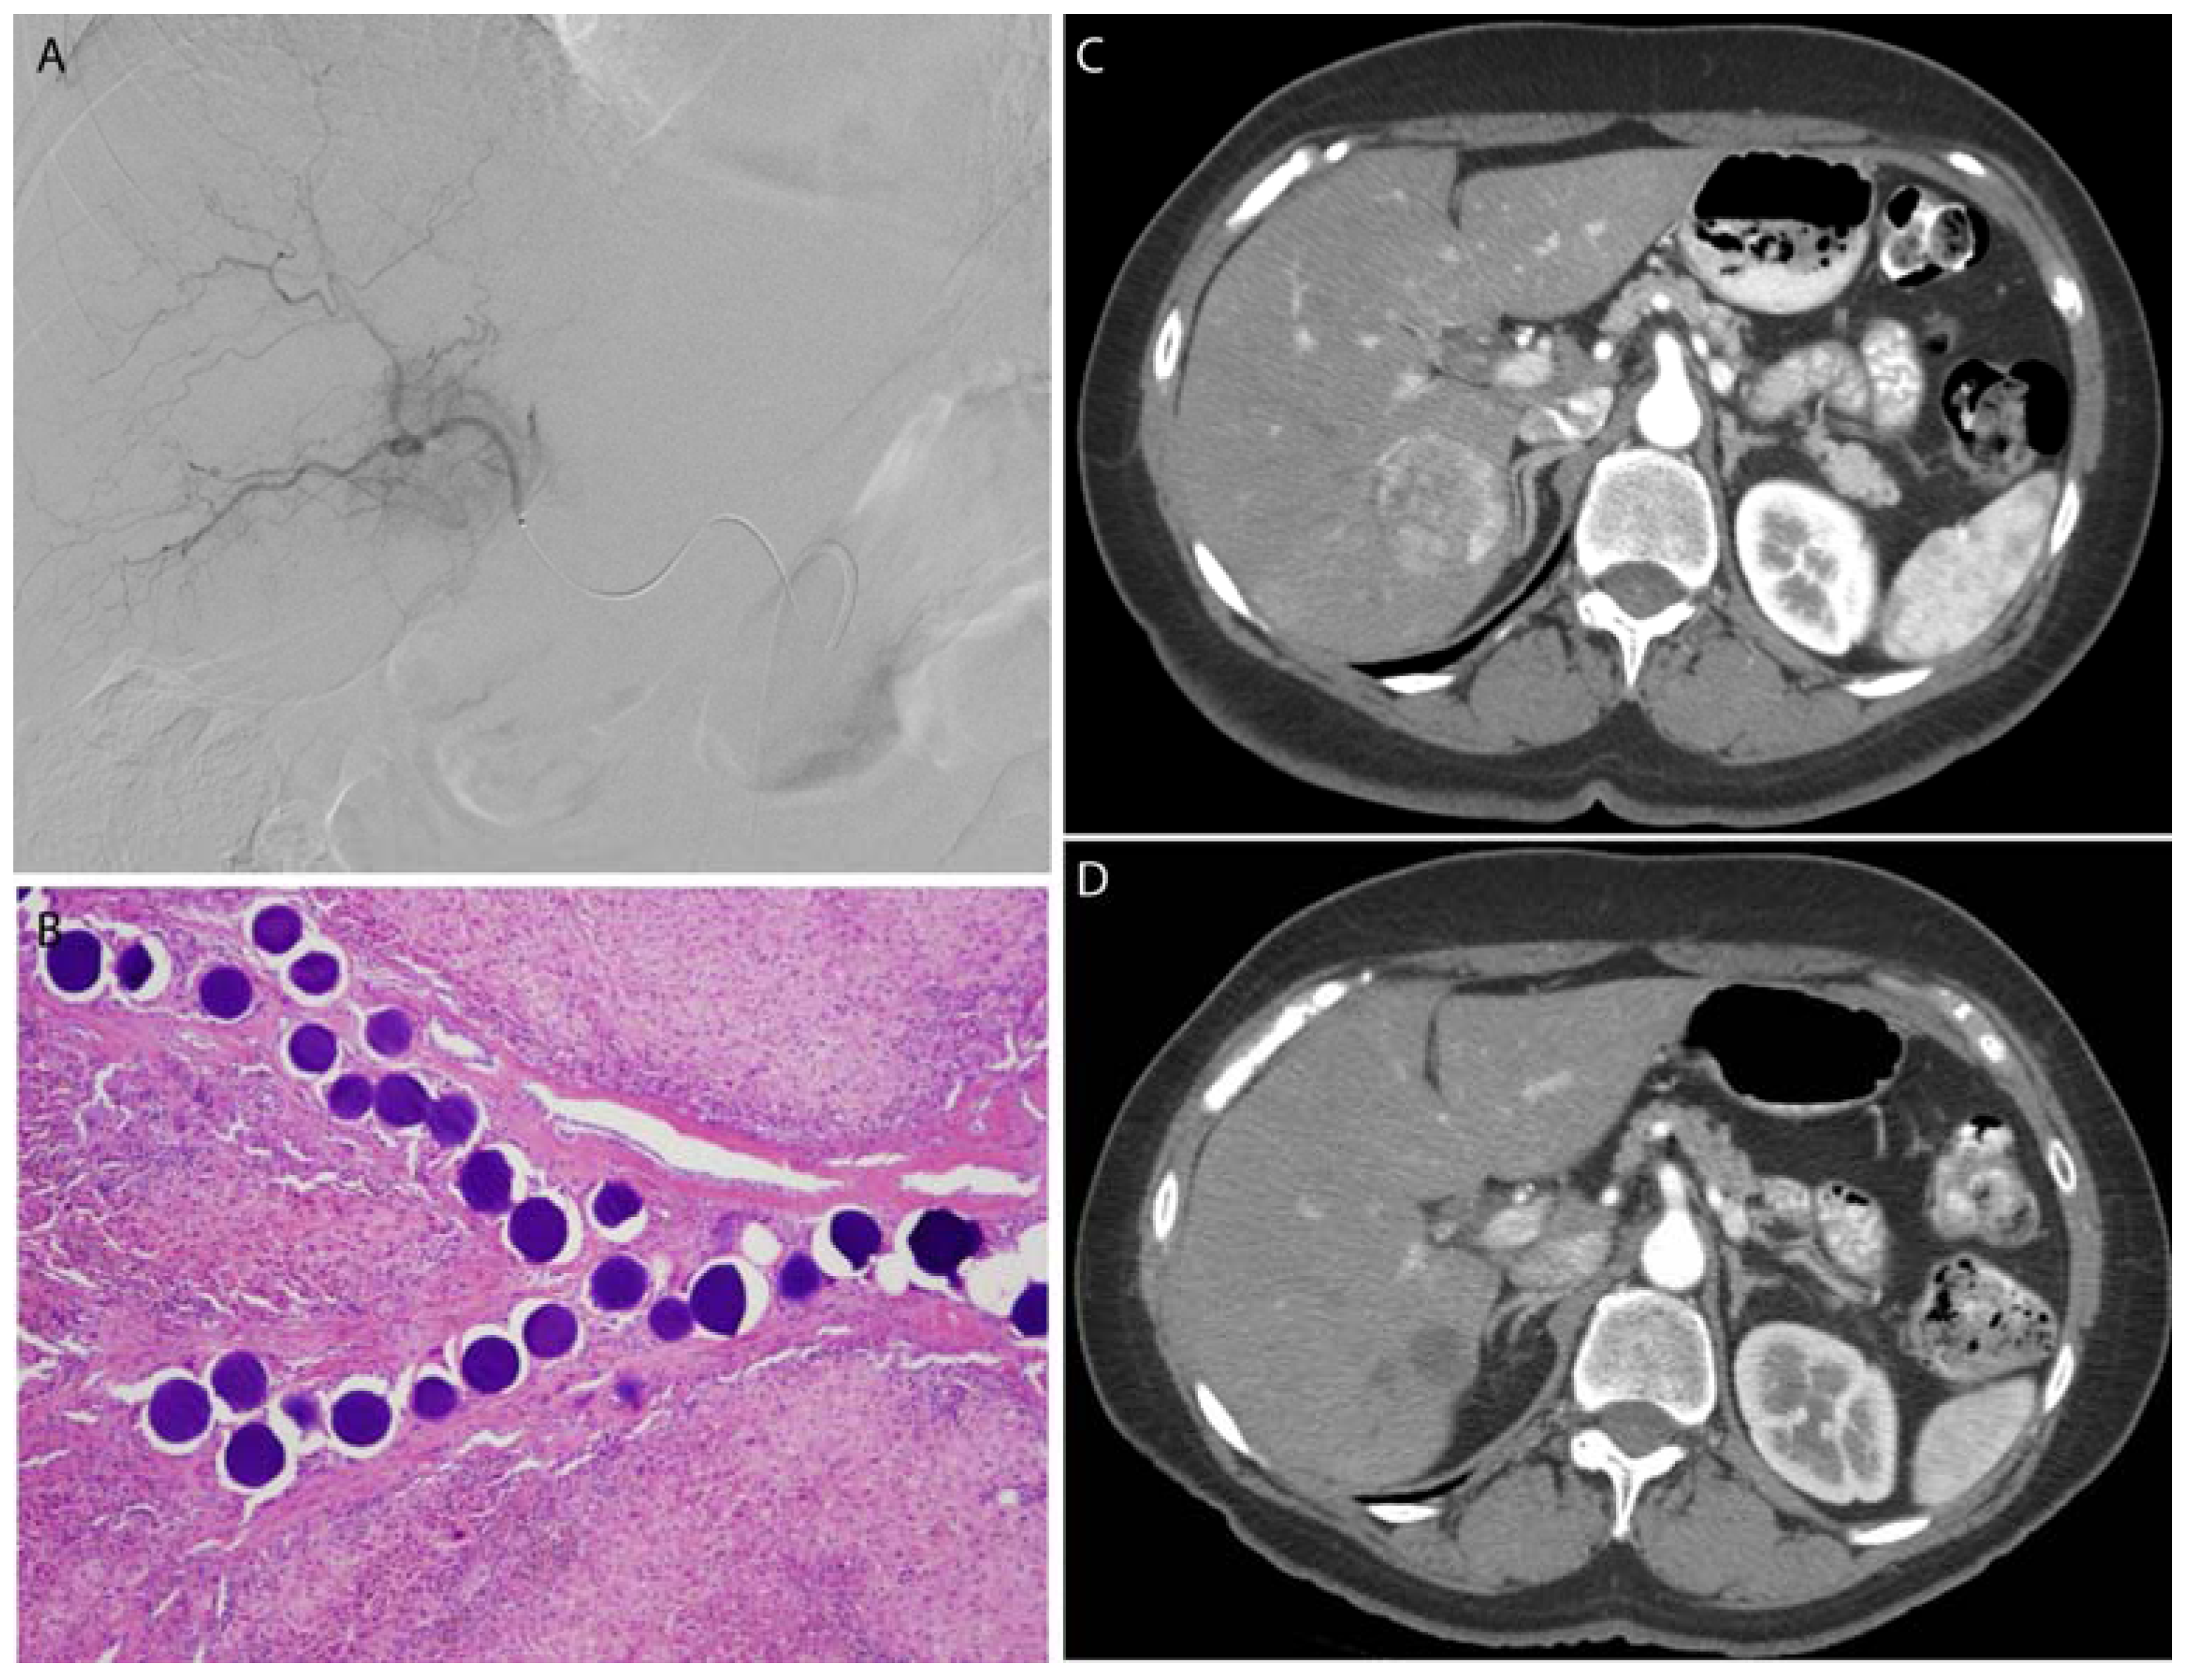

Figure 5.

A leiomyosarcoma metastasis to the liver was embolized with 100–300 μm, doxorubicin-eluting microspheres to reduce tumor size and vascularity prior to surgical resection. Selective catheterization (A) of the tumor was performed, with proper positioning confirmed by cone-beam CT (B). Post-procedure CT (C) demonstrates no residual vascularity within the lesion. Following liver resection, microspheres were identified within the blood vessels in the tumor bed without any evidence of viable metastatic tumor (D).